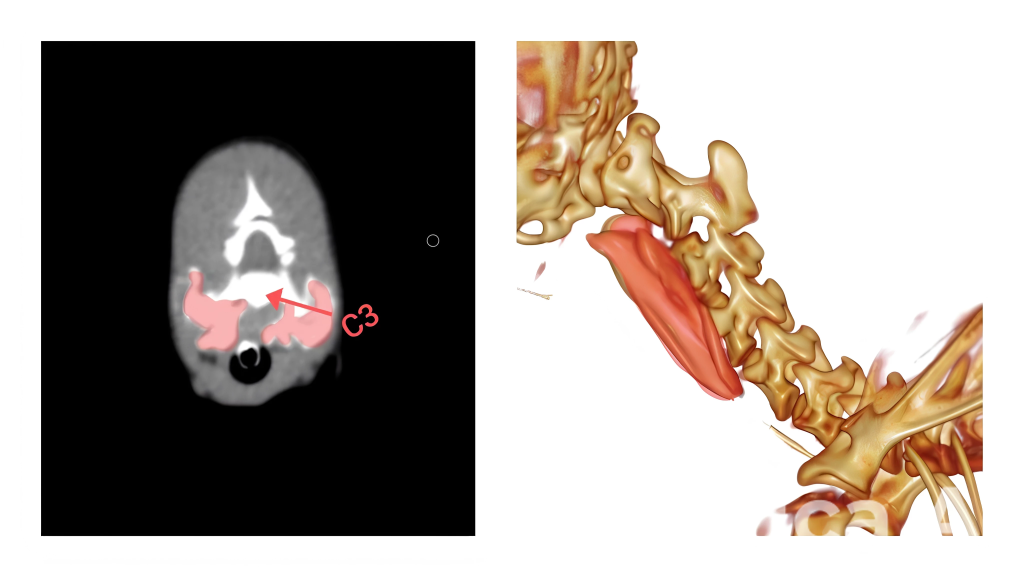

При анатомическом исследовании с окрашиванием нервных структур посредством проведения глубоких фасциальных инъекций для оценки распространения анестетика было выявлено, что прилегающая к поперечным отросткам длинная мышца головы (m. longus capitis) на уровне С3 (рядом с которой проходят спинномозговые нервы [СМН] С2-С3) начинает смещаться вентромедиально, и в области дорсального бугорка поперечного отростка третьего шейного позвонка (рис. 2) прикрепляется лестничная мышца (m. scalenus), к которой с дорсальной стороны подходит СМН С4. Далее нервы проходят поперечно по латеральной поверхности плечепоперечной мышцы (m. omotransversarius) и отдают кожные ветви от основных стволов, после чего направляются дорсально (рис. 3).

В ходе исследования было выявлено, что при введении анестетика в область фасциального пространства между длинной мышцей головы и длинной мышцей шеи на уровне дорсального бугорка поперечного отростка третьего шейного позвонка контрастное вещество чаще получало краниальное распространение. Анатомическое исследование подтвердило эффективное окрашивание вентральных спинномозговых нервов С2-С3. Такая блокада может быть полезна при проведении операций на шейном отделе позвоночника в данной области.На видео 1 и рис. 4 представлен клинический случай блокады длинной мышцы головы для проведения хирургического вмешательства по поводу атлантоаксиальной нестабильности. Пациент – собака породы йоркширский терьер, вес 1,2 кг, возраст 8 месяцев. Блокада была проведена с помощью ультразвуковой навигации.

Датчик УЗИ располагается на латеральной поверхности шеи, поперек плоскости оси шейных позвонков (рис. 5). Сканирование начинается от первого шейного позвонка, смещаясь каудально. Шейные позвонки с первого по третий имеют характерные анатомические отличия, облегчающие идентификацию необходимых структур. Стоит уточнить, что кости на УЗИ не просвечиваются, так как ультразвук отражается от поверхности кортикального слоя, формируя изображение. Первый шейный позвонок (атлант) при УЗ-сканировании латеральной поверхности шеи имеет характерные анатомические особенности. Крылья атланта имеют значительную длину и ширину, что позволяет пропальпировать их перед сканированием и установить датчик в эту область, сразу обнаружив на экране силуэт, напоминающий большую тонкую волну, вершина которой направлена перпендикулярно плоскости сканирования. Второй шейный позвонок (эпистрофей/аксис) характеризуется самым маленьким, едва различимым при сканировании поперечным отростком, но отличается довольно массивными суставными отростками. К тому же поперечный отросток эпистрофея может частично перекрывать визуализацию вентрального бугорка поперечного отростка третьего шейного позвонка. Третий и последующие шейные позвонки имеют схожую типичную анатомическую структуру. Основной мишенью визуализации при блокаде будут именно поперечные отростки шейных позвонков. В своем составе поперечный отросток в его краниальной части имеет маленький вентральный бугорок, который при сканировании будет определяться как небольшой выступ, направленный к плоскости сканирования под углом примерно 45°. В каудальной части также имеется более длинный дорсальный бугорок, который чаще обращен к плоскости сканирования перпендикулярно. Таким образом, чередуя вентральные и дорсальные бугорки, можно безошибочно определить необходимый нам анатомический ориентир.

При визуализации дорсального бугорка третьего шейного позвонка можно увидеть фасцию, прилегающую к поперечным отросткам, в виде гиперэхогенной линии, отходящую перпендикулярно (при этом параллельно сканированию). Введение спинальной иглы осуществляется с вентролатеральной стороны в фасциальное пространство между длинной мышцей шеи и длинной мышцей головы до соприкосновения с поперечным отростком (рис. 6, 7).